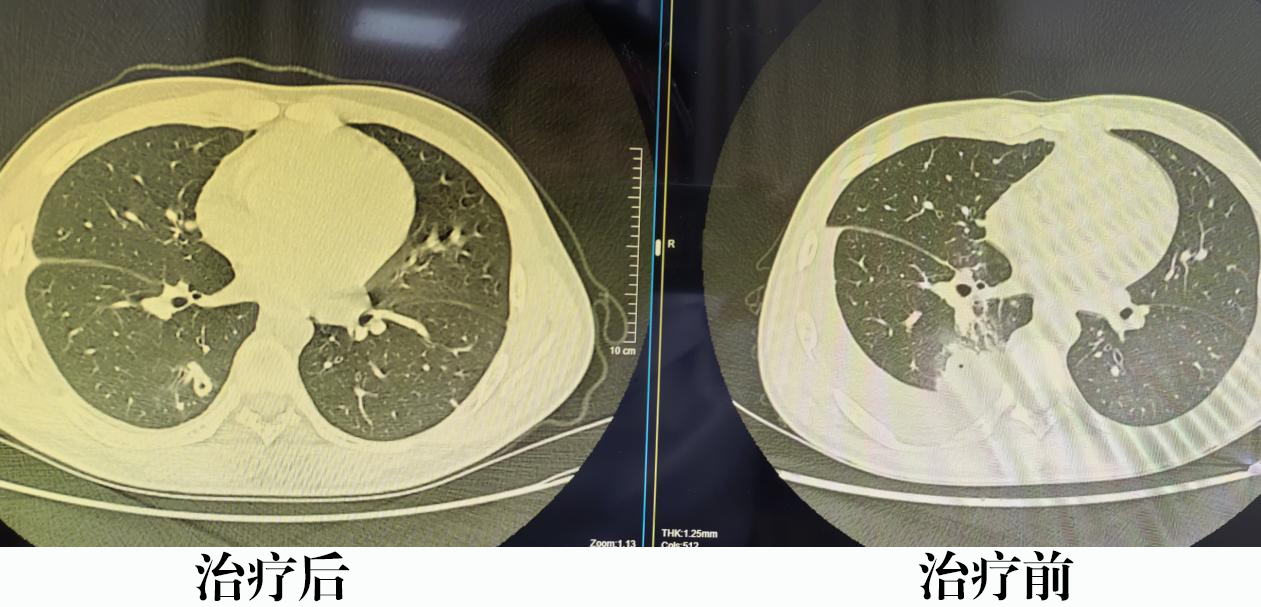

诊断明确后,李小雪医生为患者制定了针对性治疗方案,旨在抗寄生虫治疗的同时,处理由此引发的嗜酸性粒细胞性肺炎与肺泡出血。

经治疗,患者肺部影像学表现显著改善,嗜酸性粒细胞水平明显下降,目前已顺利出院。呼吸科团队将继续随访,确保疗效巩固,助力患者早日完全康复。